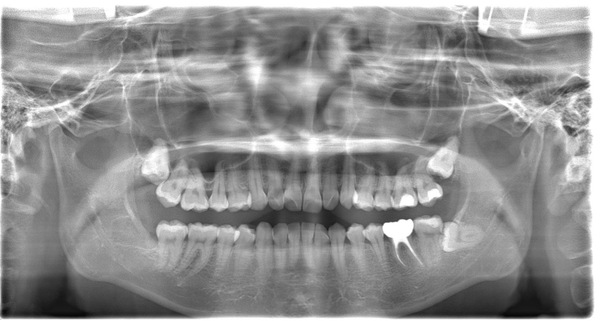

こちらは比較用初診時X線写真です。

治療前後を比較してみると、順調に骨が回復してきていることがわかります。しかし、まだ根と根の間、根分岐部と呼ばれる部分の骨が完全には上がってきておりません。

このまま骨が上がらない可能性もありますが、今回は上がってくる可能性が高いと判断し、患者様とも確認をしつつ引き続き年単位で経過を見ていきます。

こちらが根管治療終了後から1年3ヶ月後のX線写真です。

完全に骨が回復したと言って良い状況となりました。